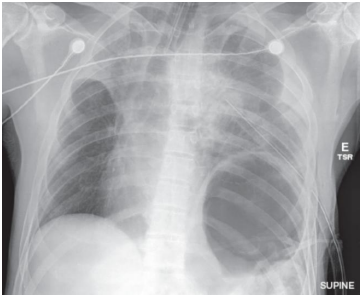

Paciente masculino, 35 anos, vítima de politraumatismo após acidente automobilístico, é admitido no pronto-socorro. Ao exame inicial, apresenta-se intubado e com dreno torácico inserido no hemitórax esquerdo devido a suspeita de pneumotórax. Os sinais vitais incluem pressão arterial de 90/60 mmHg, frequência cardíaca de 120 bpm, frequência respiratória de 30 irpm e saturação de oxigênio de 88% em ventilação mecânica. Foi realizada a seguinte radiografia de tórax:

Enunciado 4376187-1 Fonte: Sabiston Tratado de Cirurgia / Courtney M. Townsend et al. 20° edição - Rio de Janeiro: Elsevier, 2019.

Com base no caso clínico acima e nos achados da imagem, o diagnóstico mais provável é: